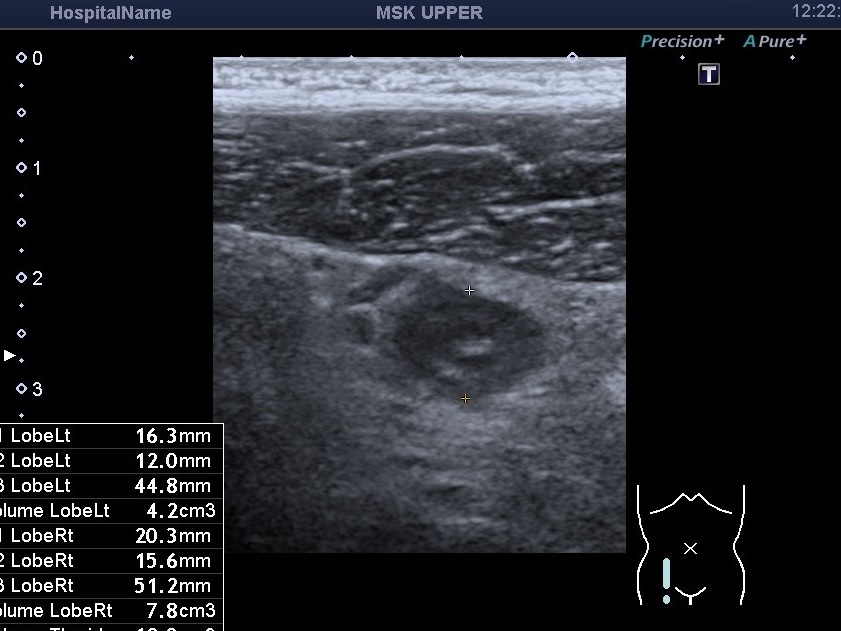

На снимках представлен случай острого аппендицита у молодого мужчины. Боли при этом были не сильные, со слов пациента, он проходил с ними 5 дней. При этом пациент обращался к гастроэнтерологу в частную клинику и при обследовании врач не обнаружил признаки острого аппендицита. Но УЗИ органов брюшной полости врач назначил. На УЗИ был выявлен увеличенный аппендикс с ещё охранённой послойной структурой, который не сжимался при компрессии датчиком и был при компрессии болезненным. Вокруг была изменённая жировая клетчатка и увеличенные мезентериальные лимфатические узлы. Пациент был в тот же день направлен к хирургу и прооперирован. Хирург подтвердил, что был уже флегмонозный аппендицит. Таким образом, ещё бы пару часов и аппендикс с гноем бы разорвался(перфорация) и вызвал такое осложнение, как перитонит, состояние с угрозой жизни пациенту.